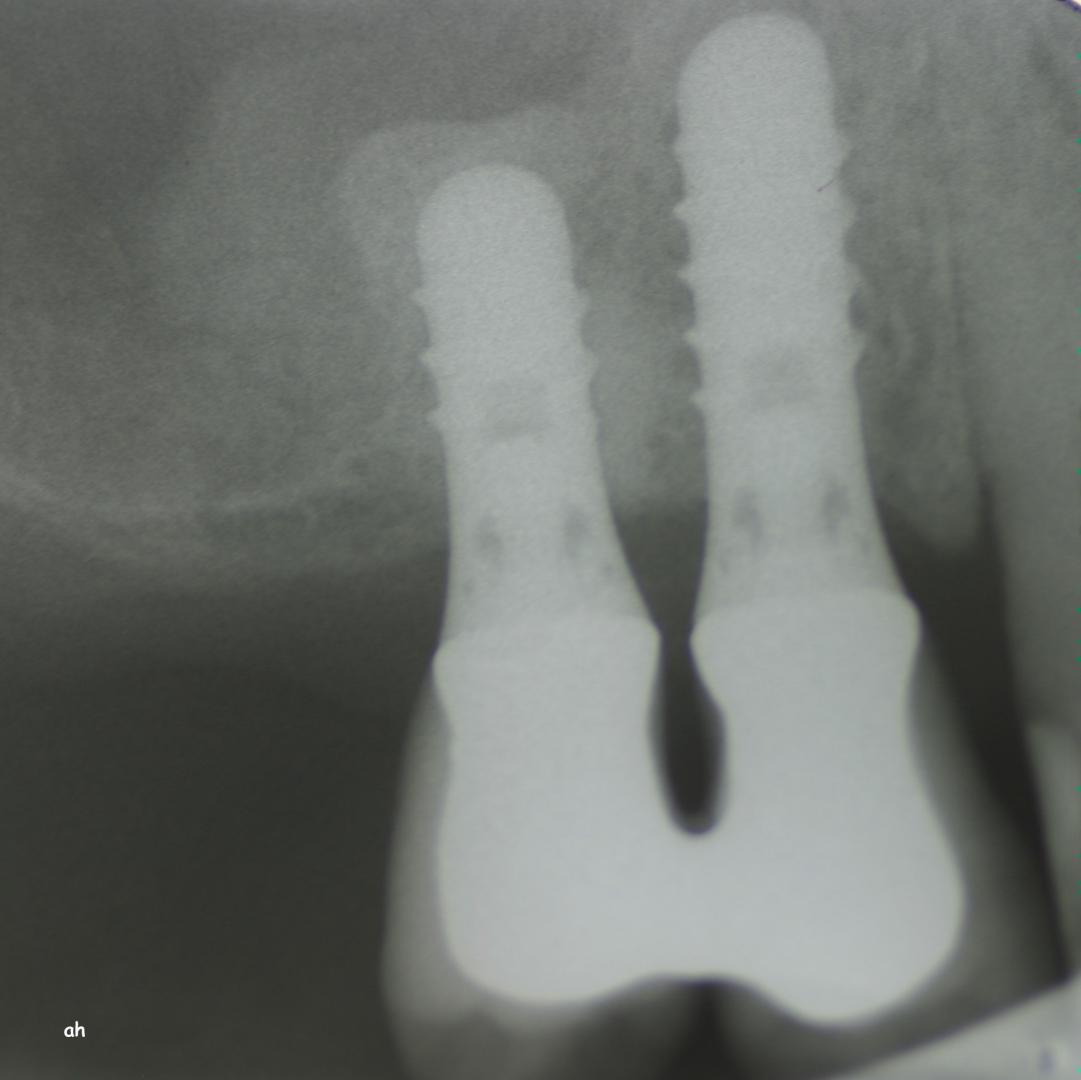

Exemple 12: Ici la pose de deux implants est envisagée, mais la hauteur d'os est insuffisante pour le deuxième implant. Le sinus (qui est une cavité creuse) est à moins de 6 mm de la surface de l'os. Idéalement il faudrait 10 mm d'os.

Exemple 12: Il faut donc relevé le sinus avec une greffe d'os avant de poser l'implant (Sinus lift).

Exemple 12: Les moignons vissés sur les implants 6 mois plus tard.

Exemple 12: Les couronnes en place.